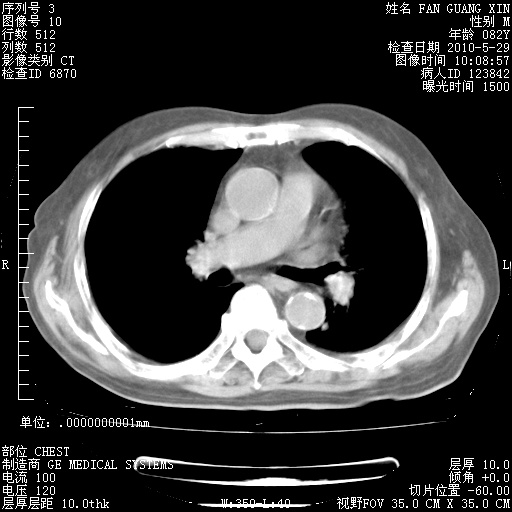

再治疗10天后的肺部CT 纵膈窗

阅读此次胸部CT,肺间质渗出性改变较入院时有吸收。目前从体温、白细胞、中性分叶明显增高,肯定存在细菌感染(发生医院感染哦,若无消化道及泌尿系统等感染的依据,肺部感染可能大)。若你院头孢哌酮舒巴坦钠耐药率较高,同意你的方案,若48小时体温仍高,可考虑使用碳青霉稀类抗菌药物,同时可予超声雾化、注意滴数时加大液体量。白蛋白33.30g/L较低哦,需加强营养等支持治疗。

肺部体征:呼吸25次/分,心率100次/分,呼吸音增粗。无干湿罗音。

血常规:15.36×10 [sup]9[/sup]/L  N0.92  L0.036  M0.045 ESR 27mm/h。

血生化:白蛋白33.30g/L  球蛋白23.67g/L  CRP 32.82mg/L 肝肾功能正常。电解质正常。

从白细胞总数和中性比例看好像合并感染。肺部纹理好像比上次多,支气管炎?其他感染?

加用抗菌药物左氧氟沙星+哌拉西林他唑巴坦?前几年我们医院头孢哌酮舒巴坦钠应用较滥,感觉疗效不如哌拉西林他唑巴坦。